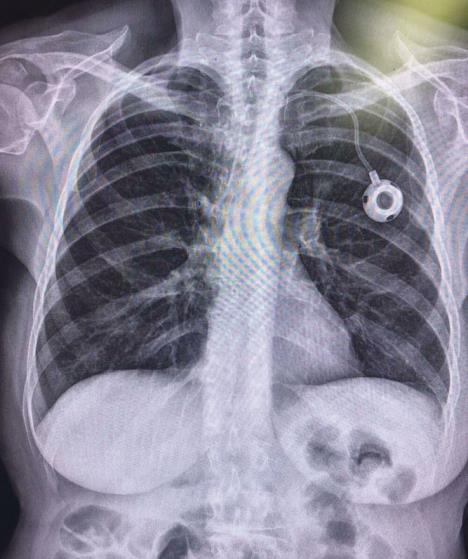

Port-a-cath, ili jednostavno port, je medicinski uređaj koji omogućava siguran i lak pristup venama za razne vrste lečenja, posebno kod onkoloških pacijenata. Postavlja se ispod kože i povezuje sa velikim venama blizu srca, što omogućava dugotrajnu i efikasnu terapiju.

0805-portnarendgenskomsnimkupacijenta-foto-privatna-arhiva---ff.jpg

Port na rengenskom snimku pacijenta Foto: Privatna Arhiva

Port je mali uređaj sastavljen od tri dela:

Telo porta – glavni deo gde se aplikuje terapija

Septum – silikonski deo kroz koji se lekovi ubrizgavaju

Kateter – cev koja vodi lekove direktno u krvotok.